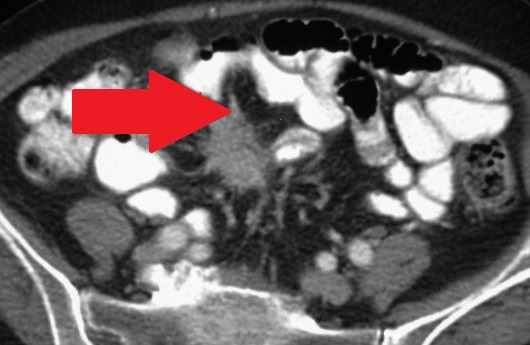

Mesenteric root infiltration — Absolute contraindication for cytoreductive surgery (Courtesy Dr. V. Penopoulos)